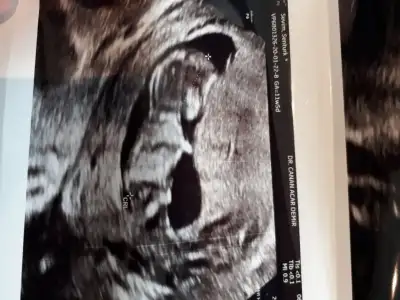

Buda net değil fotoyu cekerkenmi bozuluyor acaba

13 haftalikken bir doktor kız dedi 1 hafta sonra başka bir doktor erkek dedi 3 hafta sonra kız diyen doktor yine kız dedi ama hiçbiri net konuşmuyorHayırlısı çok net değil usg bakalım kızmı erkekmi şimdi kaç haftalık hamilesiniz dr ne zaman kız yada erkek dedi devaml gittiğiniz drmu kız yada erkek dedi

Bencede kız 2 defa kız demiş aynı dr13 haftalikken bir doktor kız dedi 1 hafta sonra başka bir doktor erkek dedi 3 hafta sonra kız diyen doktor yine kız dedi ama hiçbiri net konuşmuyor

Sanki kız gibi ama emin değilim nubu karanlık kalmış 12 yada 13 haftada paylaşın emin olmak istiyorum

Kız gibi geldi bana da